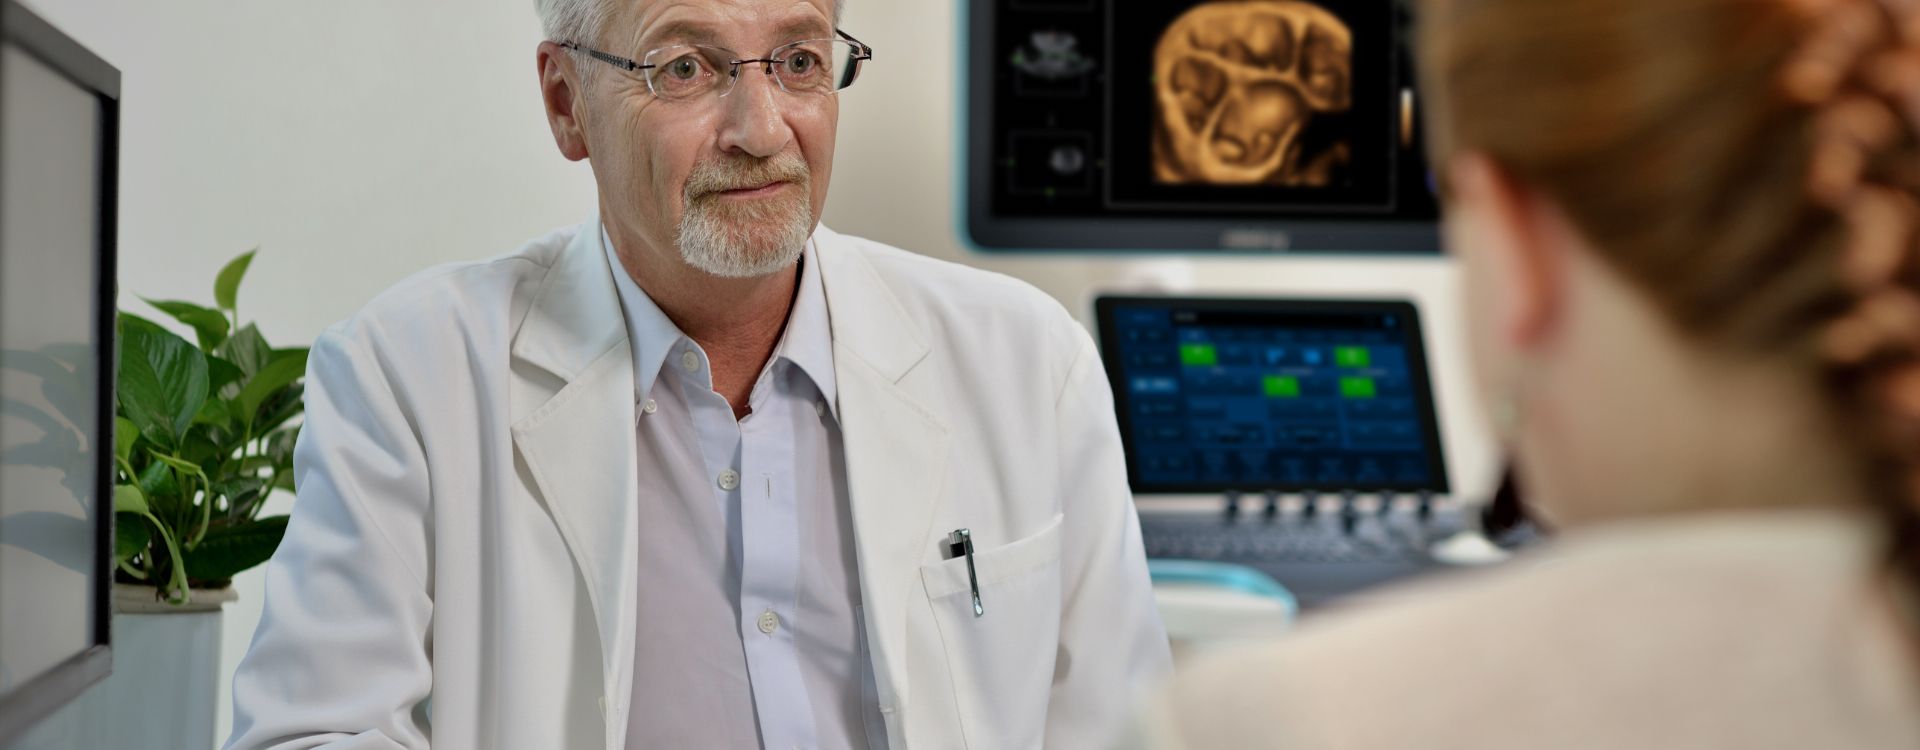

Mit den allgemeinen Bildgebungsl?sungen der Resona-Serie von Mindray k?nnen Arzt und ?rztin genauer und effizienter diagnostizieren sowie bessere Behandlungserfolge erzielen, durch umfassende geteilte Anwendung der Sonden und effiziente klinische Anwendungstools.

Das medizinische Umfeld ist komplexer geworden, die Zahl der schwierigen F?lle und Workloads gestiegen.